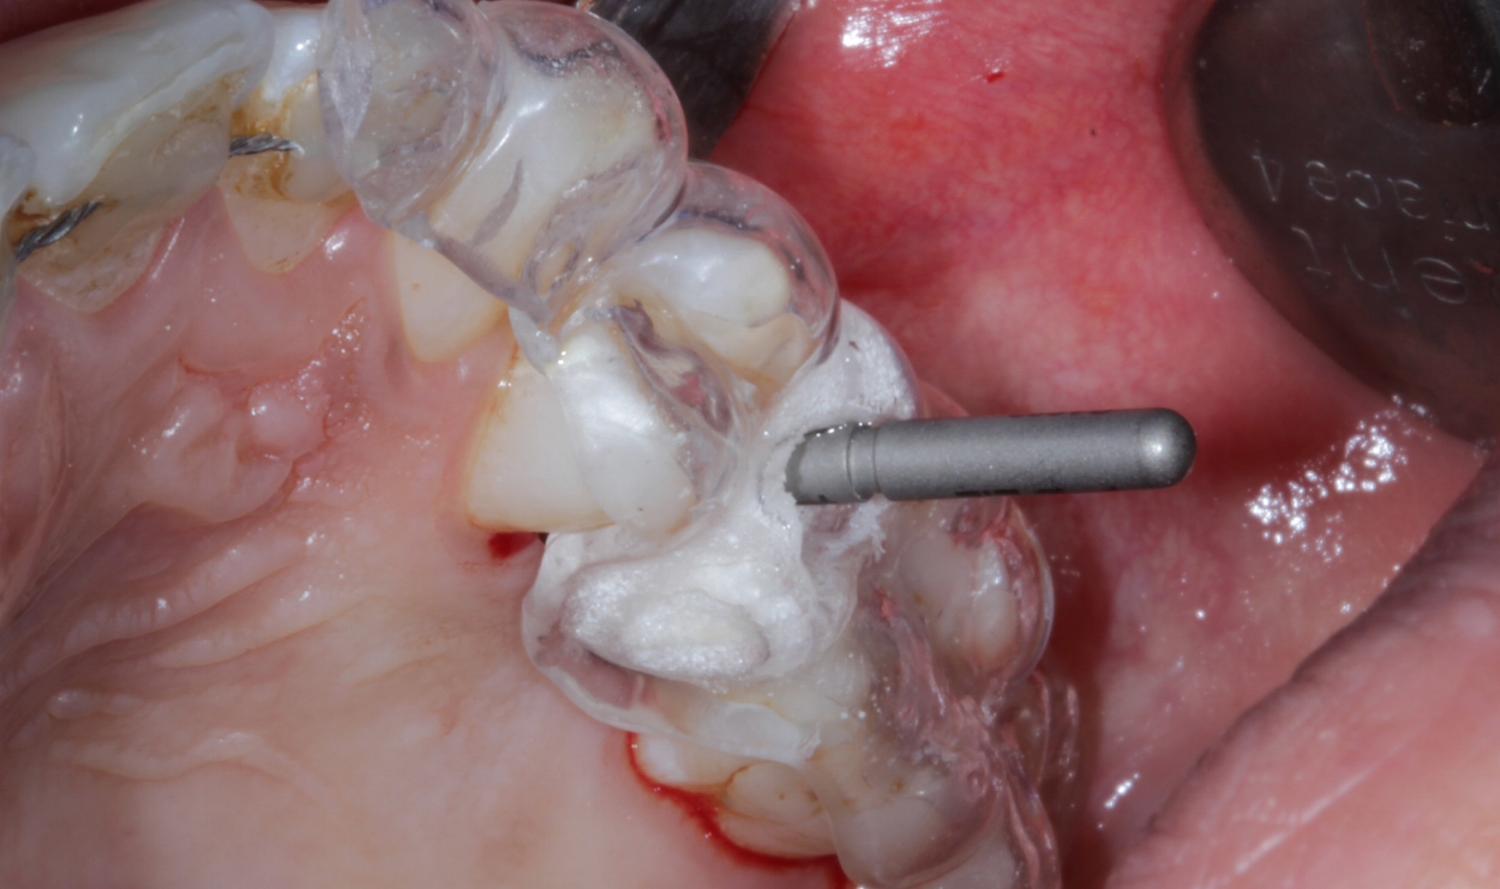

The complete implant restoration package, this includes a custom gold anodised titanium abutment, clinical screw and an all ceramic crown for a fixed price of only £293!

As our customer you will receive; the finest “custom”, hybrid, two-piece implant abutment system. This gives you the amazing strength and reliability of a Titanium connection while still benefiting from the beauty of Zirconia.

The main complaint of the stock 'Ti Base' is that they have a sudden and uncontrolled emergence profile in relation to the crest of the bone, this often causes far too much pressure on the soft tissue and in some cases the bone, resulting in blanching and subsequently resorption. There are also concerns over their short height for strength and bond surface.

Customised margins depth- easy cement removal to avoid Peri-implantitis

Perfectly shaped emergence